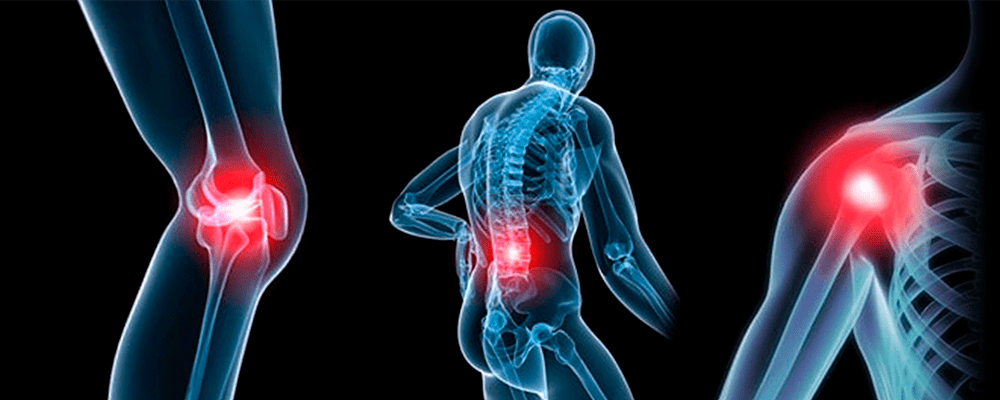

Анатомические рисунки суставов человека